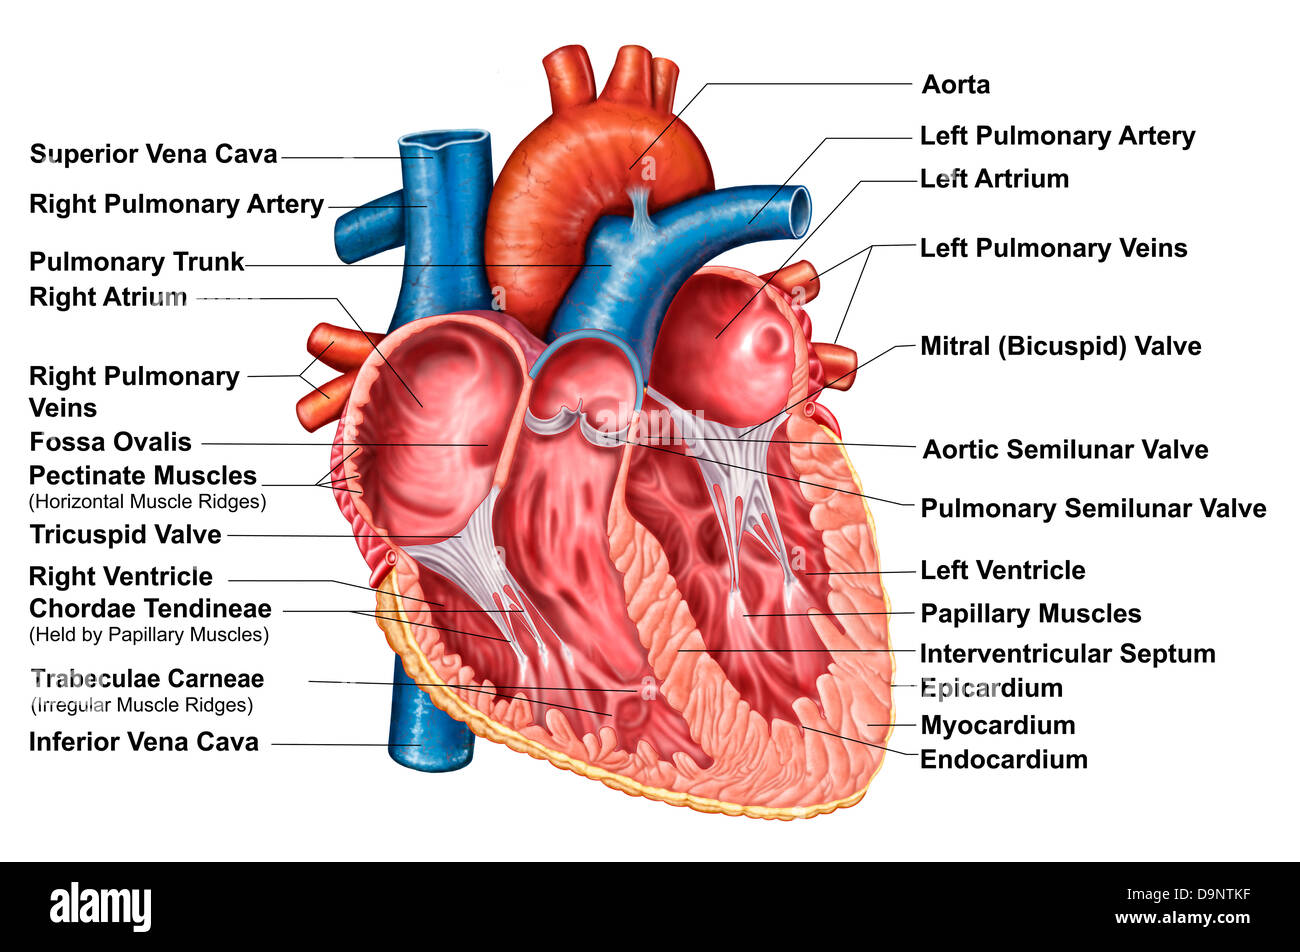

Internal view of the human heart. Stock Photohttps://www.alamy.com/image-license-details/?v=1https://www.alamy.com/stock-photo-internal-view-of-the-human-heart-73471736.html

Internal view of the human heart. Stock Photohttps://www.alamy.com/image-license-details/?v=1https://www.alamy.com/stock-photo-internal-view-of-the-human-heart-73471736.htmlRFE7EWXG–Internal view of the human heart.

Anatomy of heart interior, frontal section. Stock Photohttps://www.alamy.com/image-license-details/?v=1https://www.alamy.com/stock-photo-anatomy-of-heart-interior-frontal-section-57643363.html

Anatomy of heart interior, frontal section. Stock Photohttps://www.alamy.com/image-license-details/?v=1https://www.alamy.com/stock-photo-anatomy-of-heart-interior-frontal-section-57643363.htmlRFD9NTKF–Anatomy of heart interior, frontal section.